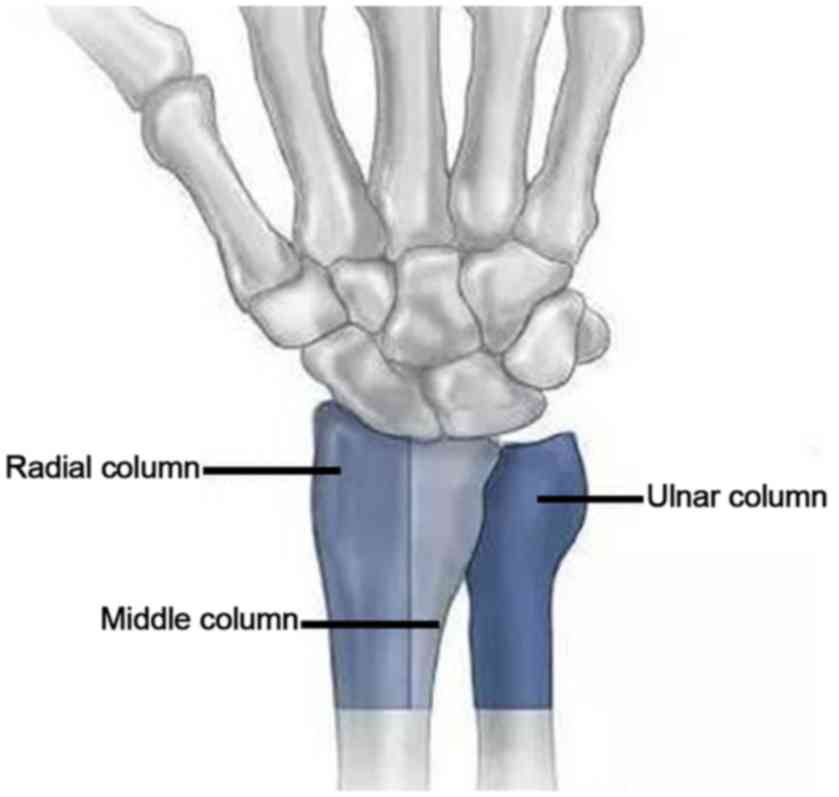

Due to differences in the extent and complexity of force at the time of injury, wrist position and bone condition, die-punch fractures may not only affect the ulnar demifacet of the distal radius but also the radial demifacet of the distal radius. These fractures include articular surface collapsed fractures and articular surface split fractures, as well as marginal fractures on the volar or dorsal side (2). According to the ‘three-column theory’ of distal radius fractures proposed by Rikli and Regazzoni (7) (Fig. 1), the die-punch fractures may be classified into the following two types: Single column and double column (Figs. 2 and 3A). A die-punch fracture is a rare occurrence. The Müller-AO classification of distal radius fractures includes die-punch fractures, although no specific system currently exists for the classification of die-punch fractures. Although certain studies have described a classification system for single-column die-punch fractures of the distal radius (2,8), the classification of double-column die-punch fractures remains to be established.

Figure 1.

Illustration of the three-column theory of distal radius fractures.